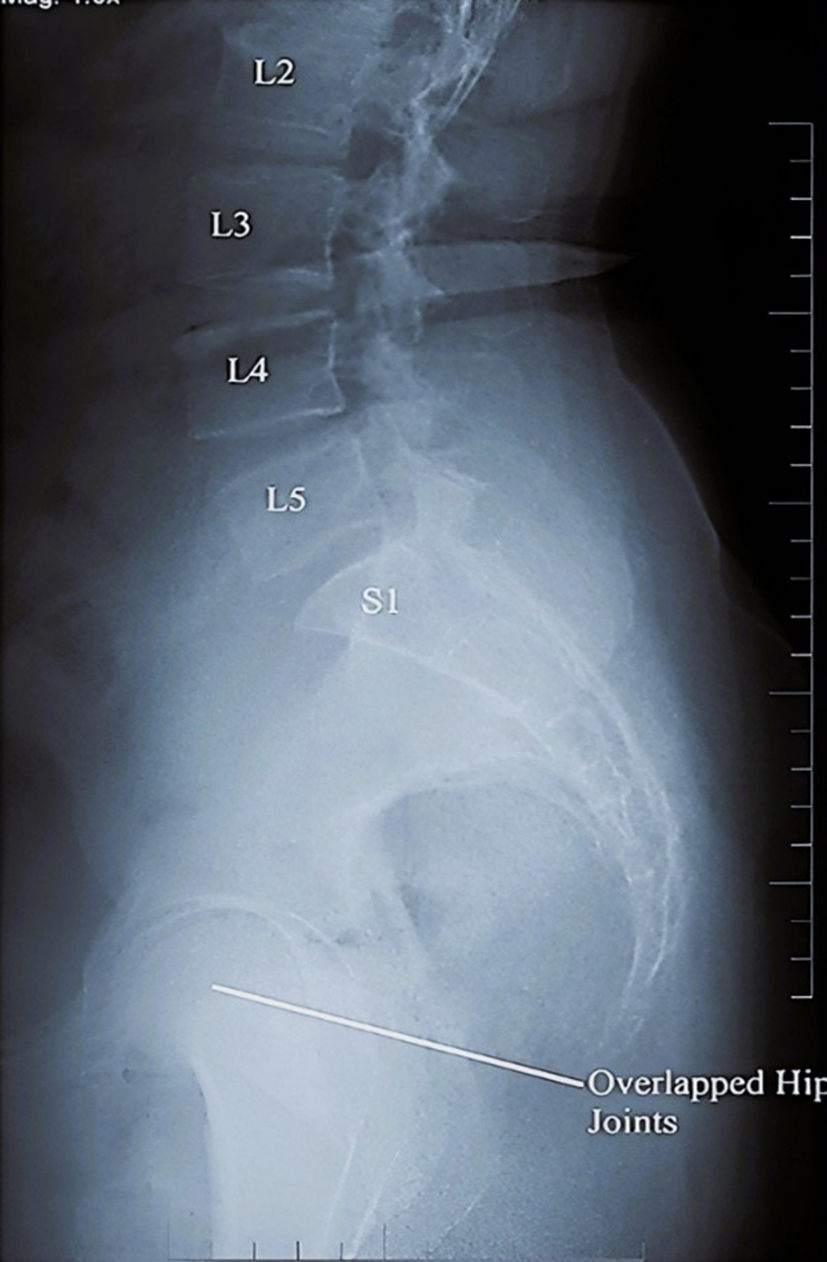

Key spinopelvic parameters include pelvic incidence (PI), pelvic tilt (PT), sacral slope (SS), and lumbar lordosis (LL). These are essential for assessing sagittal balance and spinal alignment [9]. PI, typically ranging from 30° to 80° (average 50°–55°), reflects pelvic anatomy and remains stable post-skeletal maturity; abnormal values may indicate structural imbalances. PT, generally between 10° and 15° (range 5° to 30°), measures pelvic orientation; elevated PT is often seen in spinal deformities. SS assesses the sacrum's inclination, normally 30° to 50°, with deviations indicating potential mechanical issues. LL, the inward curvature of the lower back, usually spans 40°–60° but can range from 20° to 80°; hypo- or hyper lordosis may be related to various pathologies (Fig. 1). Abnormalities in these parameters are associated with spinal malalignment, pain risk, and degenerative conditions.

Fig. 1. Standing lateral radiograph of lumbosacral spine. Panel (A): Native image showing vertebral levels (L2–S1) and overlapped hip joints. Panel (B): Same image annotated to demonstrate measurement techniques for spinopelvic parameters. Red lines indicate the superior endplate of L1, the inferior endplate of L5, and the superior endplate of S1. Perpendiculars to endplate lines are shown to illustrate lumbar lordosis (LL), sacral slope (SS), pelvic incidence (PI), pelvic tilt (PT), and vertical reference line (VRL).